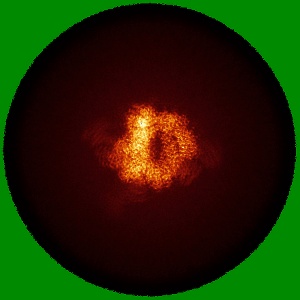

Cryo-EM Structure of HIV-1 BG505DS-SOSIP.664 Env Trimer Bound to DFPH-a.01_10R59P_LC Fab

Sample: BG505 DS-SOSIP DFPH-a.01_10R59P_LC FAB COMPLEX

Fitted models: 9q0w